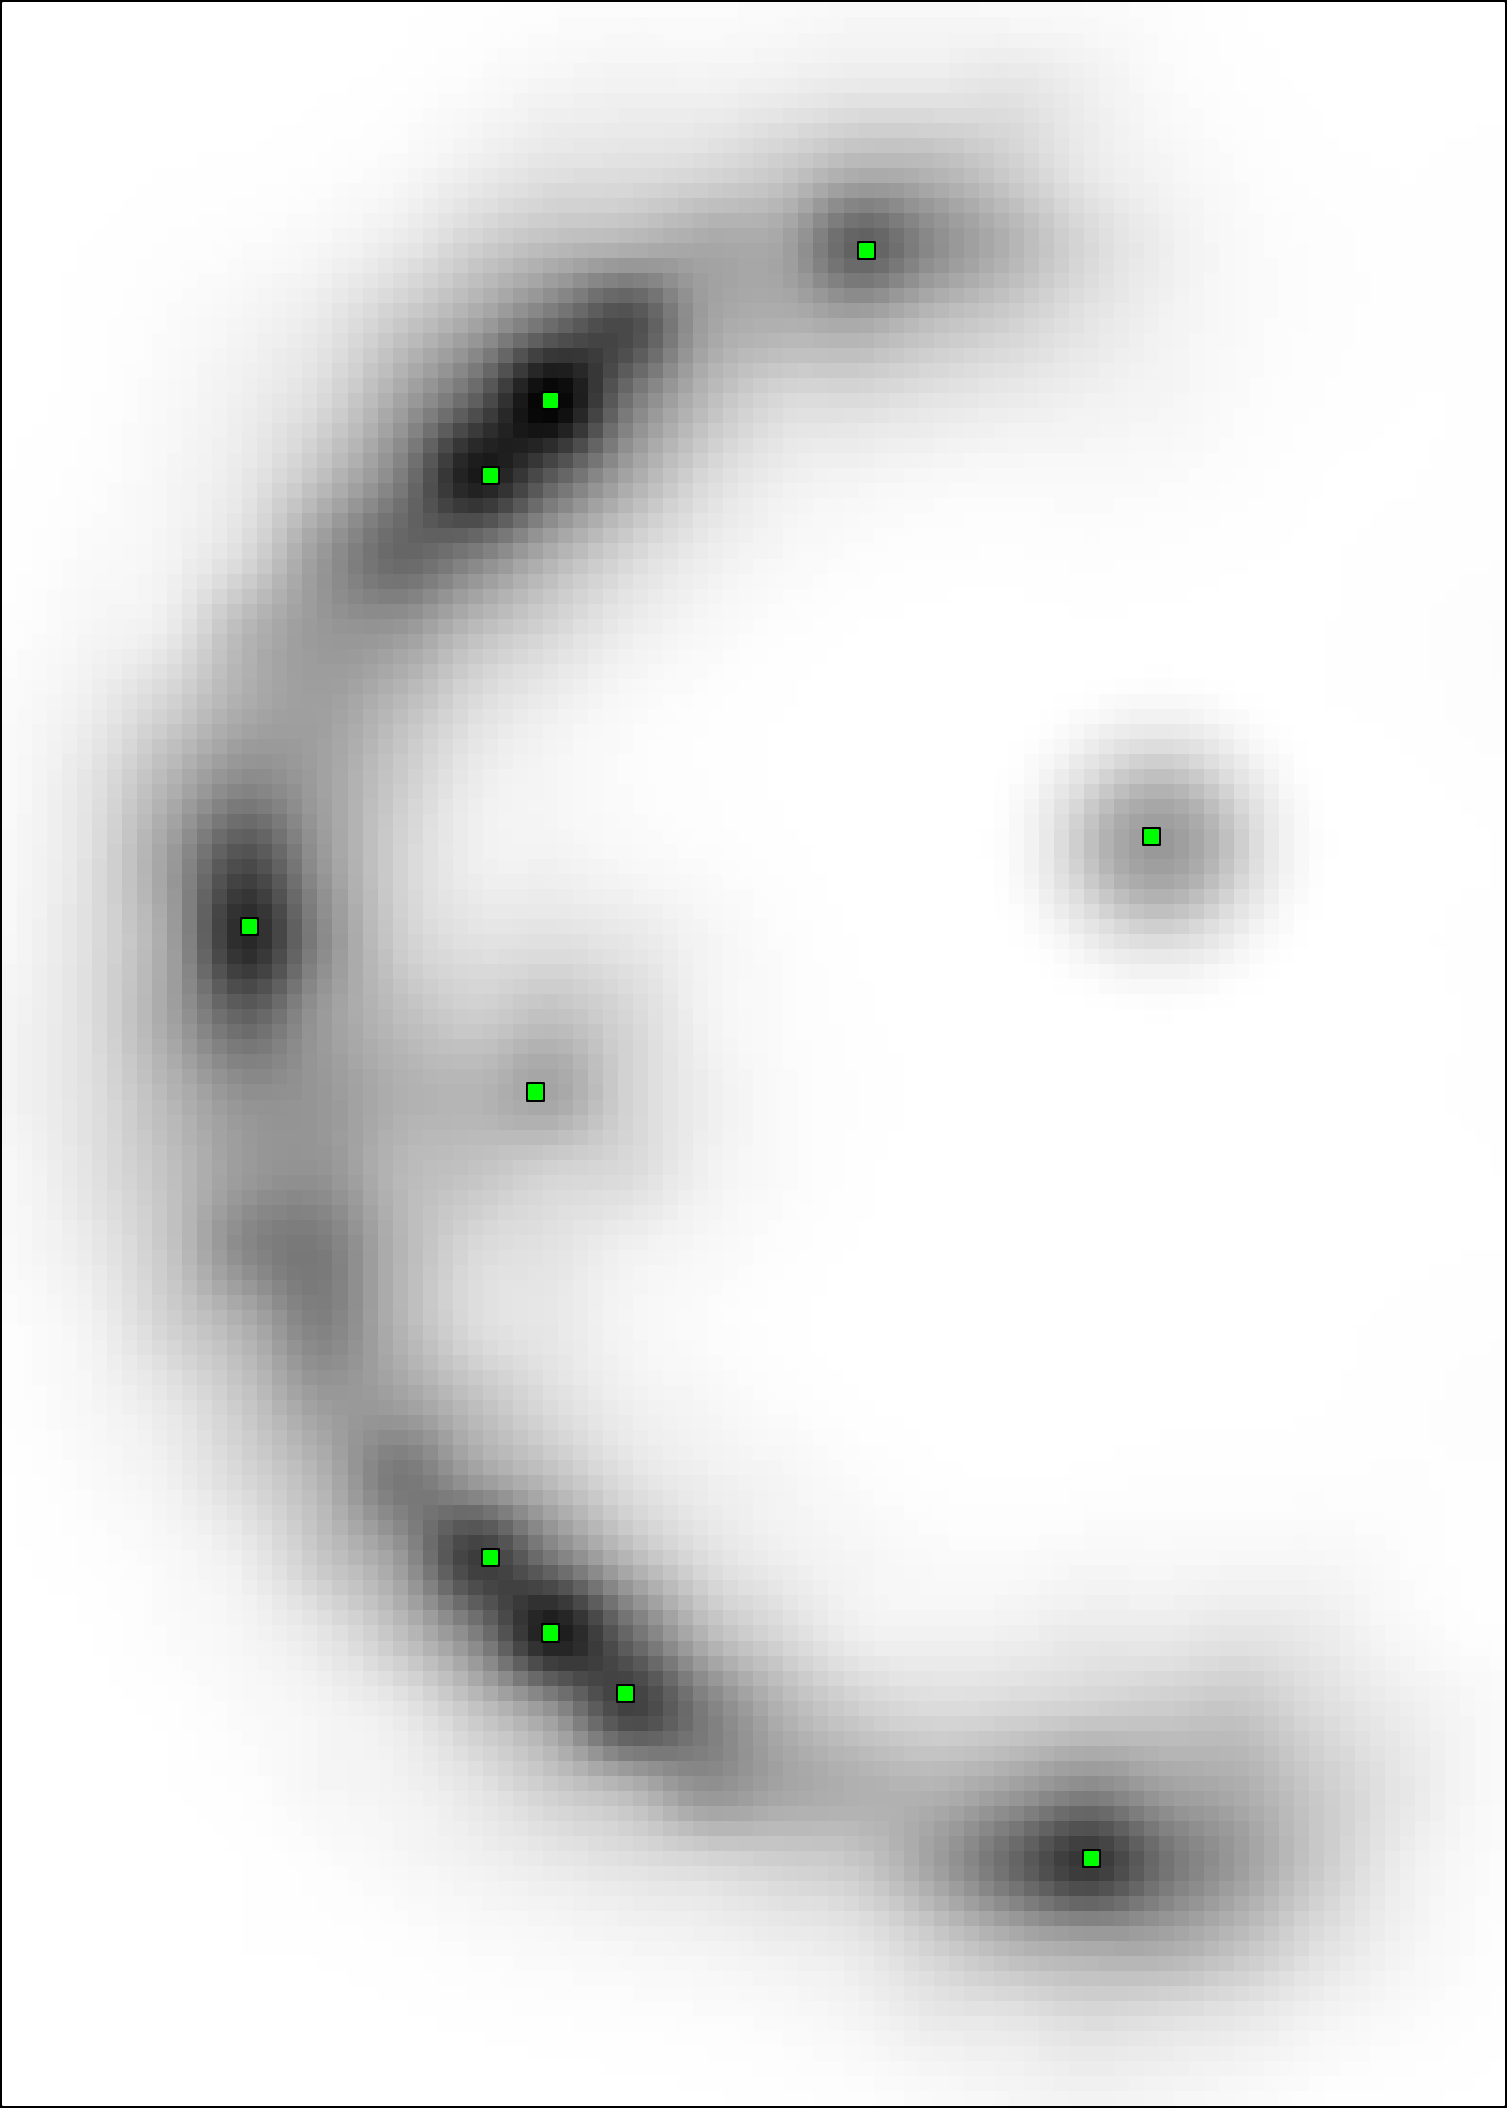

Geodesic paths are determined by back-tracing when different regions collide. The connecting geodesic is extracted minimizing at the collision grid-points. The aFM maps, i.e. ; the Voronoi index map , representing the label associated to each propagating seed; and the Tag , representing the state of each grid-point (Front, Visited, Far), are then updated within the collided regions, so that these merge as one and the front is consistent with the unified resulting region. This is continued until all regions merge.

Initialization. The seeds are aligned towards the vessels’ mid-line with a constrained gradient descent, resulting in an initial set of sources . All 26-connected components initialize the aFM maps, i.e., , , , and constitute also the initial geodesics .

Fast Marching Step. The aFM maps are updated by following an informative propagation scheme. We refer to [4] for the 3D aFM step considering the 48 simplexes in the 26-neighbourhood of the Front grid-point with minimal .

Path Extraction. Collision is detected when Visited grid-points of different regions are adjacent. A connecting is determined by linking the back-traced minimal paths from the collision grid-points to their respective sources with a gradient descent on (fig. 2). The associated integral geodesic length is computed and the connectivity in is updated in the form of an adjacency list. Lastly, the grid-points of the extracted are further considered as path seeds in the updating scheme, since furcations can occur at any level of the connecting minimal paths.

Fast Updating Scheme. A nested aFM is run only in the union of the collided regions using a temporary independent layer of aFM maps, where , , and . Ideally, the nested aFM is run until complete domain exploration, however, to speed up the process, the propagation domain is divided into the solved and unsolved sub-regions, and the update is focused on the latter (fig. 2). The boundary geodesic values of equal the geodesic distances at the collision grid-points. Lastly, the aFM maps are updated as: , , and .

3.2 Connected Geodesic Paths as Vascular Tree

Representative examples of degraded synthetic images from SVT and the respective GT are shown in fig. 4 together with the connected graphs extracted by VTrails. Analogously, the same set of images are reported for the real images TOF and CTA in fig. 4. Qualitatively, the extracted set of connected geodesic paths shows remarkable matching with the provided GT in all cases. First, we verify the acyclic nature of the graph. We found no cycles, degenerate graphs and unconnected nodes, meaning that the extracted connected geodesic paths represent a connected geodesic tree. Precision and recall are then evaluated for the identified branches. Also, error distances are determined as the connected tree’s binary distance map evaluated at GT. Average errors () precision and recall are reported (meanSD) in table 1. Note that no pruning of any spurious branches is performed in the analysis.